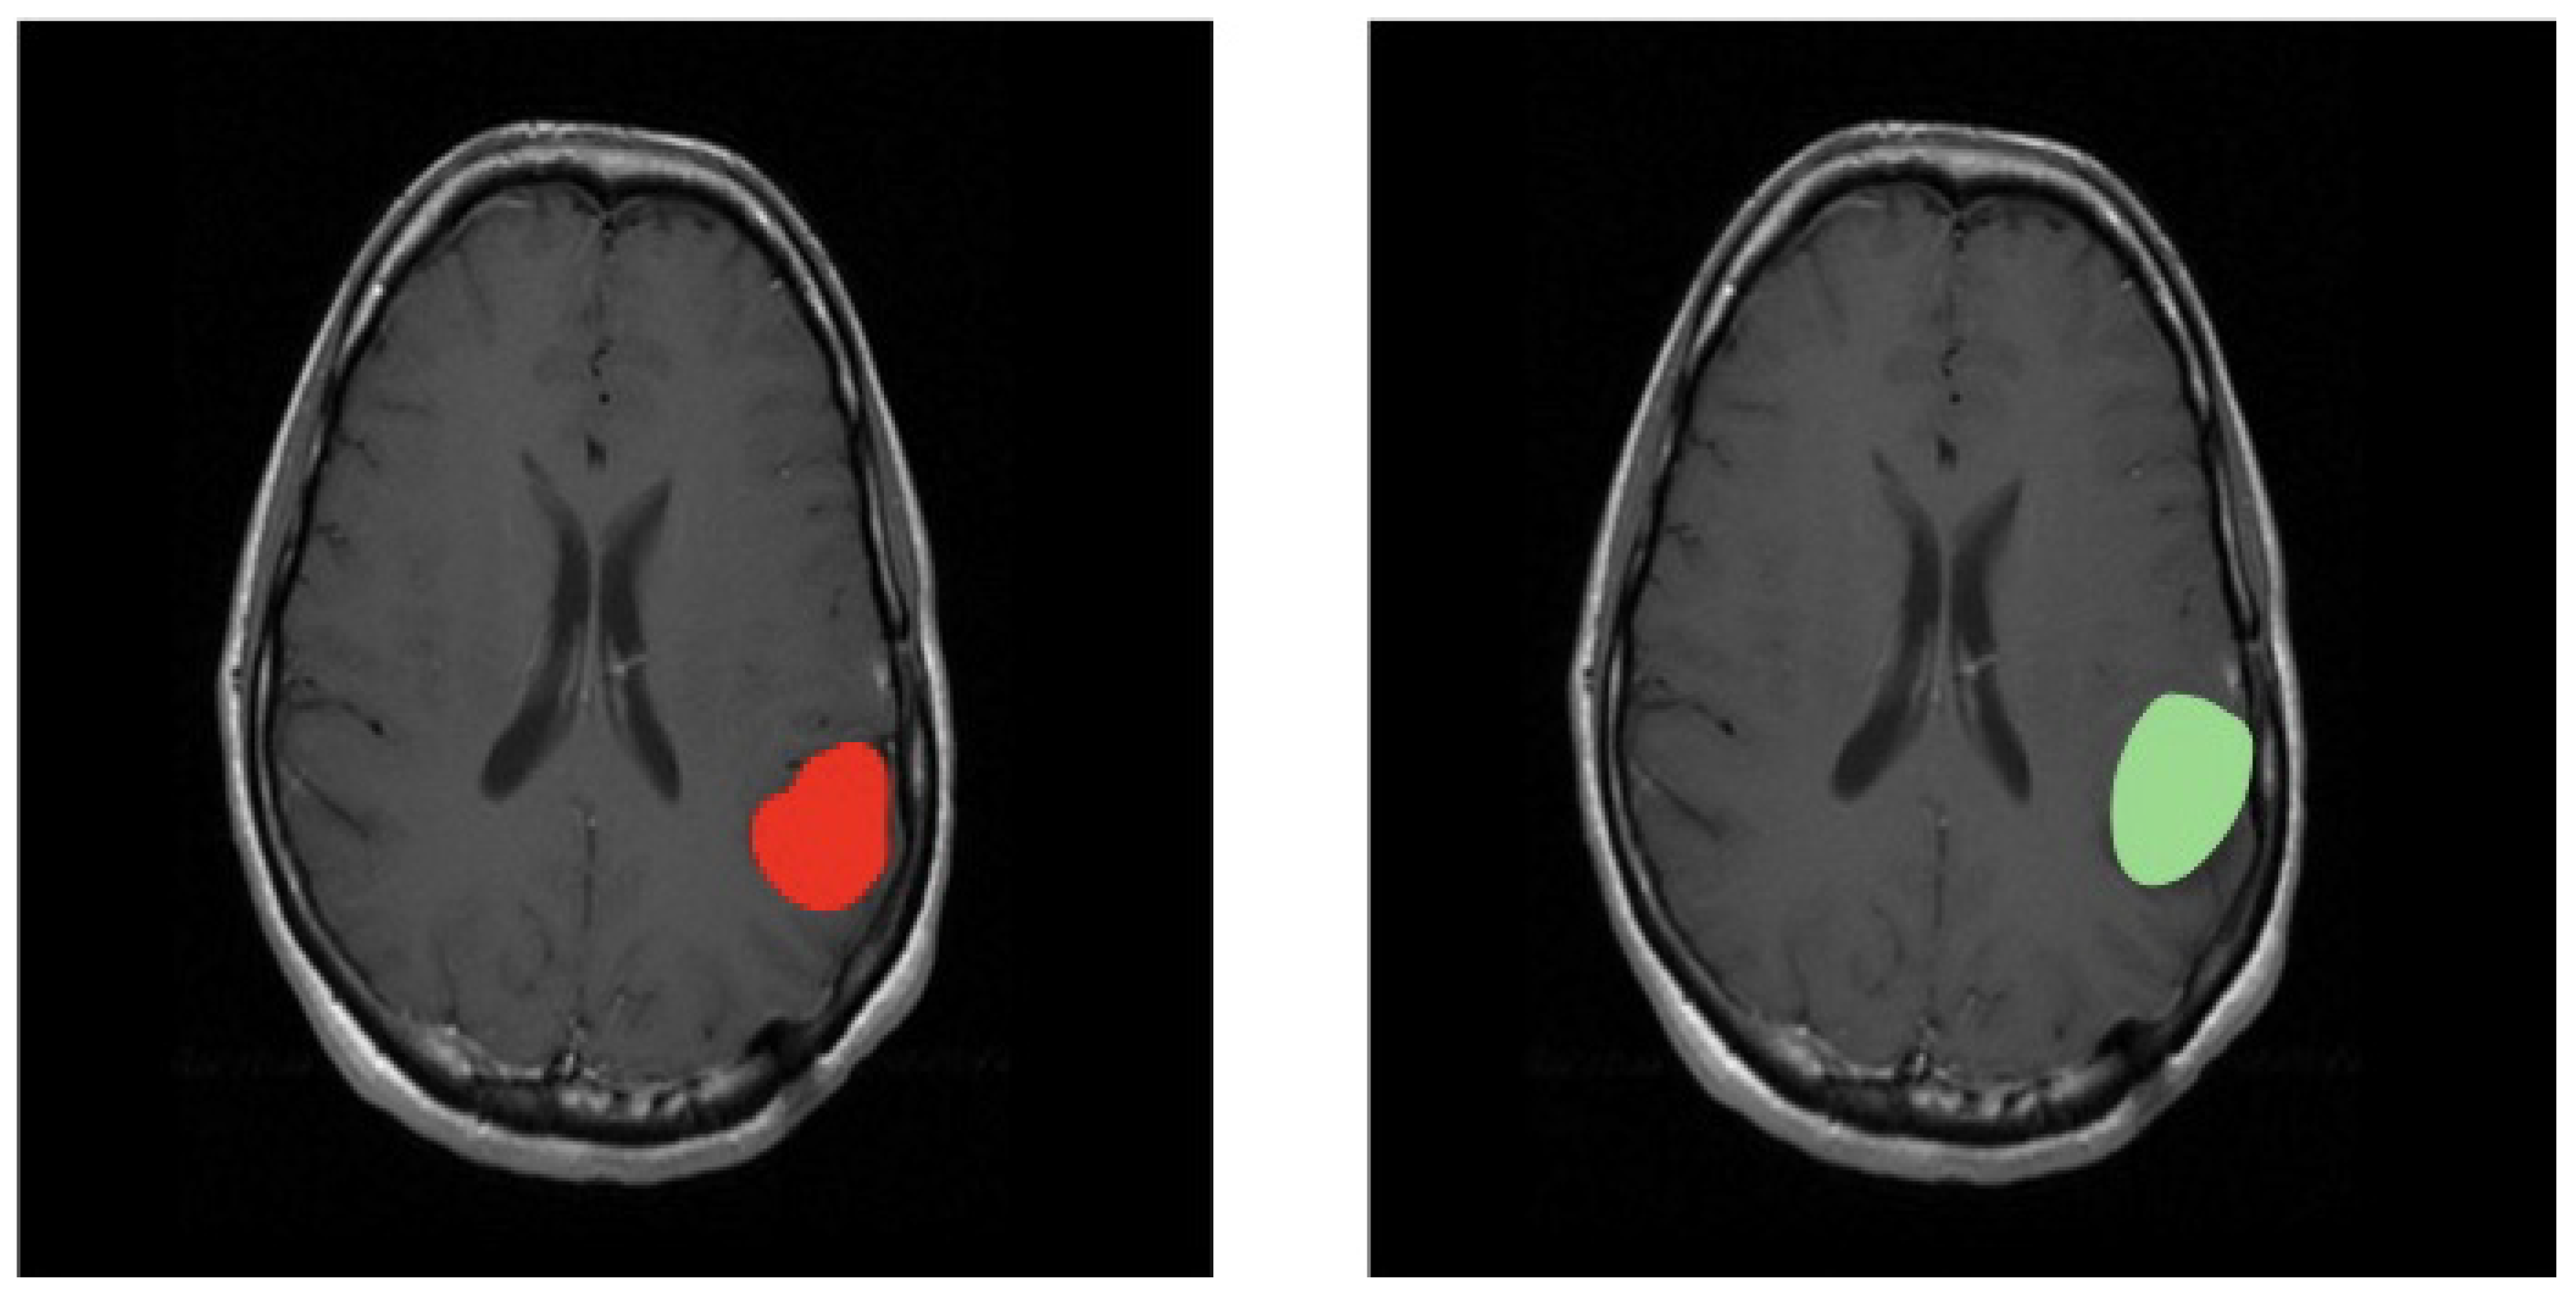

3.1. First Scenario

3.2. Second Scenario